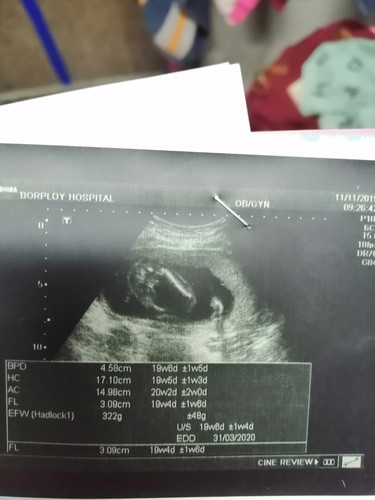

แบบนี้หญิงหรือชายค่ะแม่ๆเราดูไม่ค่อยออก ที่มีลูกศรชี้

ลูกสาวค่ะแม่ ไม่มีจู๋โผล่